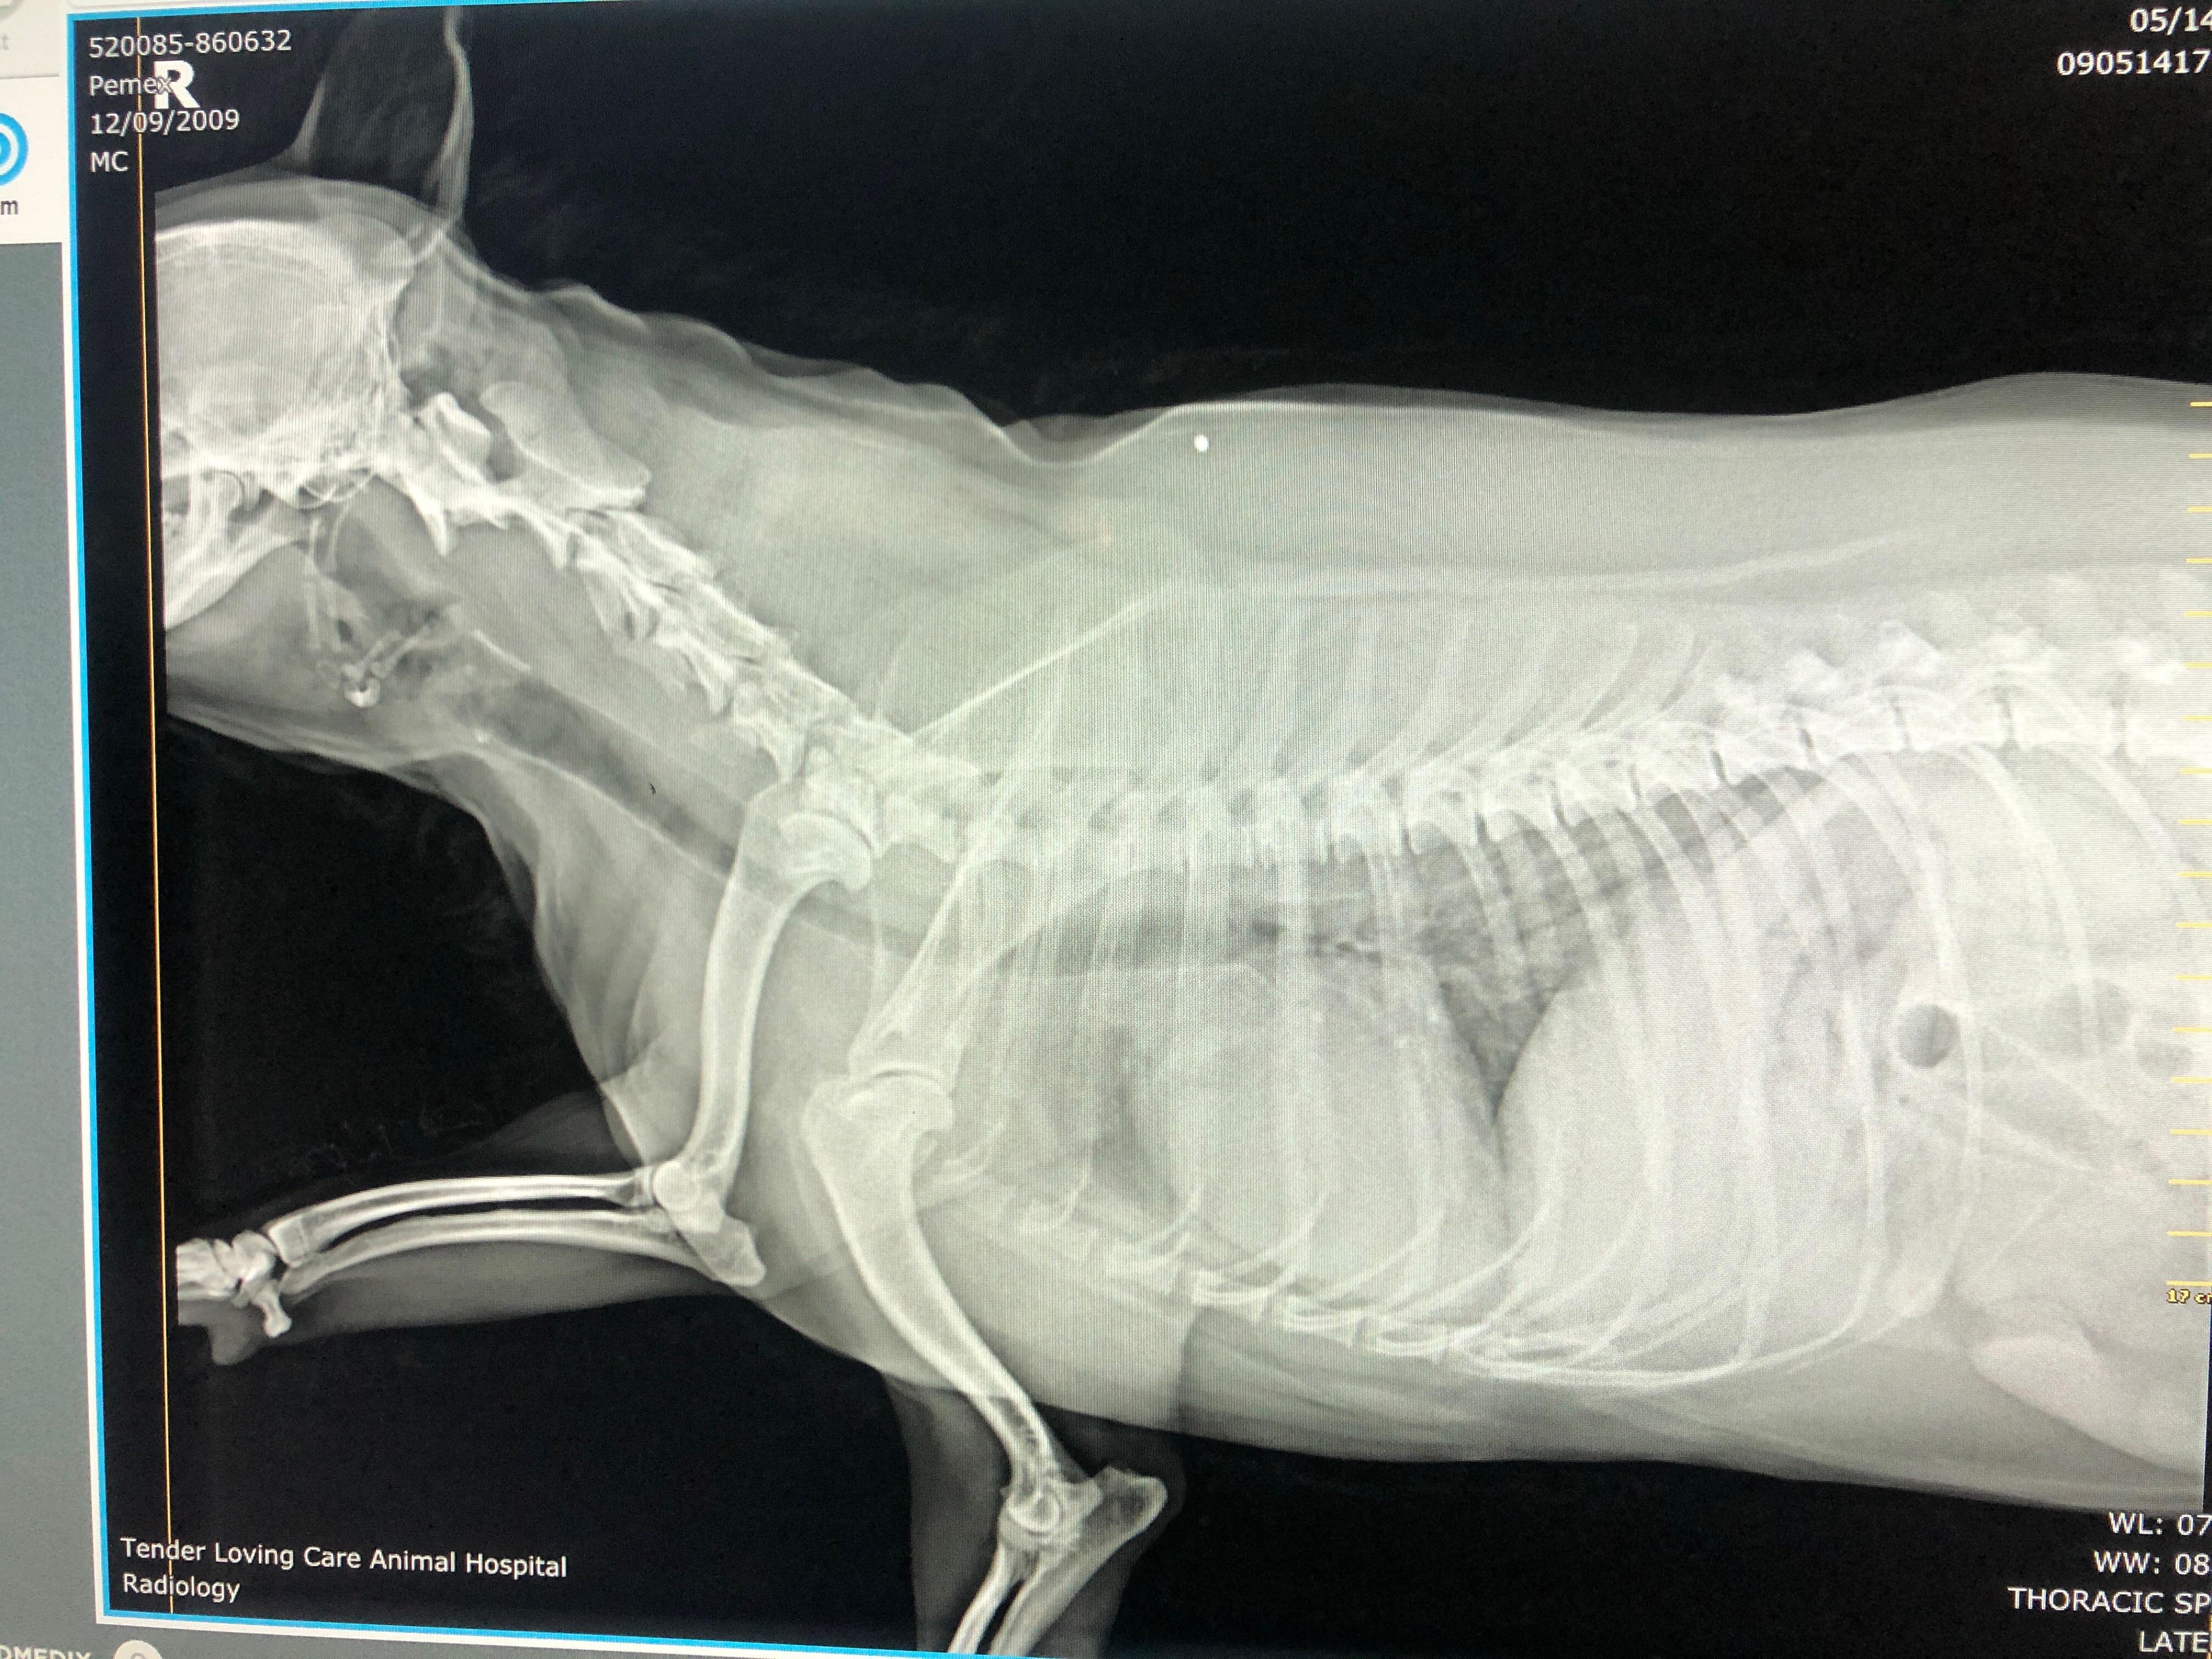

13yo dog came in to check a mass on the abdomen. DVM suspected it was Dog Chest Rads Central venous line (bottom left), nasogastric feeding tube (middle), and pleural chest tube (top right). In patients with effusion, soft tissue opacity or fluid accumulation will be present within the interlobar fissures, which will be widest peripherally and thinner centrally. Severe alveolar infiltrate with a prominent air bronchogram is present in the right middle and right caudal lung lobes secondary. Dog Chest Rads.